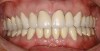

Figure  1  Natural tooth wear.

Figure 1